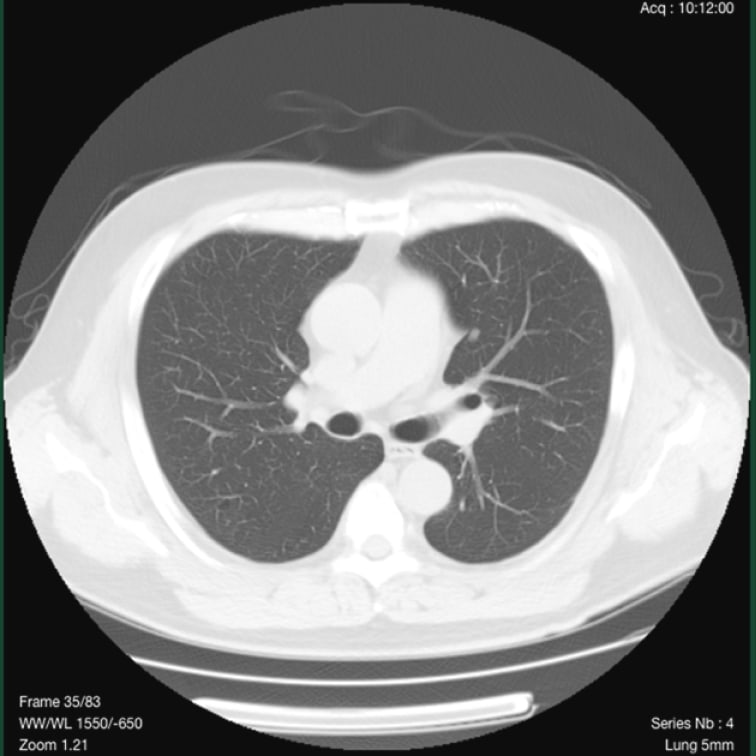

標準線量CT